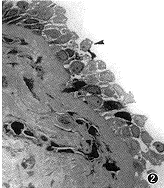

第1次冷冻后2周鼻粘膜上皮肿大、变圆、淡染,细胞间排列松散,可见许多细胞分离、脱落,上皮层明显变薄(图2)。

图2 第一次冷冻2周后鼻粘膜光镜观察,上皮分离、脱落(▲),上皮层变薄。×40